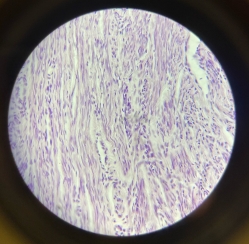

Smooth Muscle

Smooth Muscle

Smooth Muscle